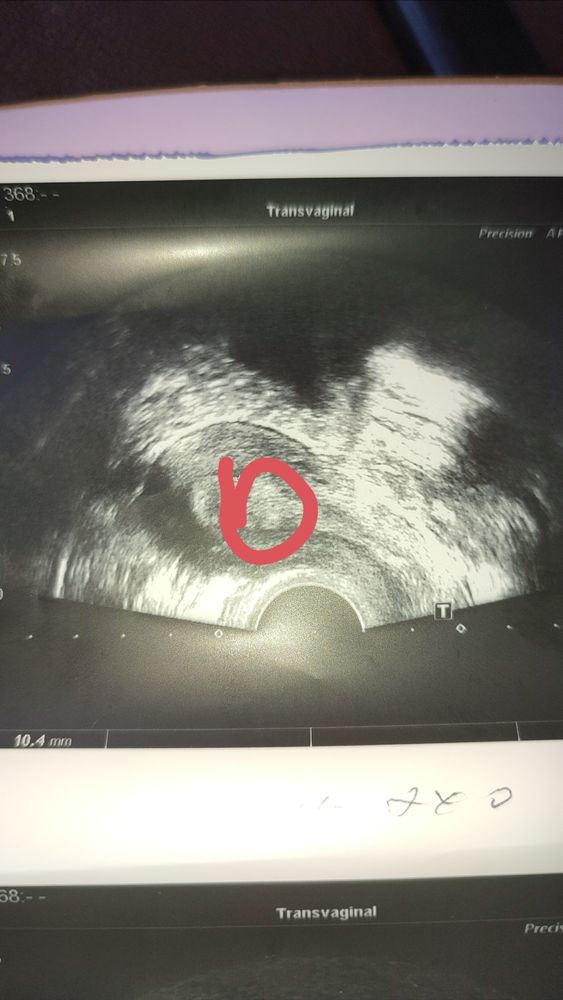

Что это за кружок?

Кулакова Александра, у вас все чисто. Ничего нет. Чёрные точечки эта структура матки